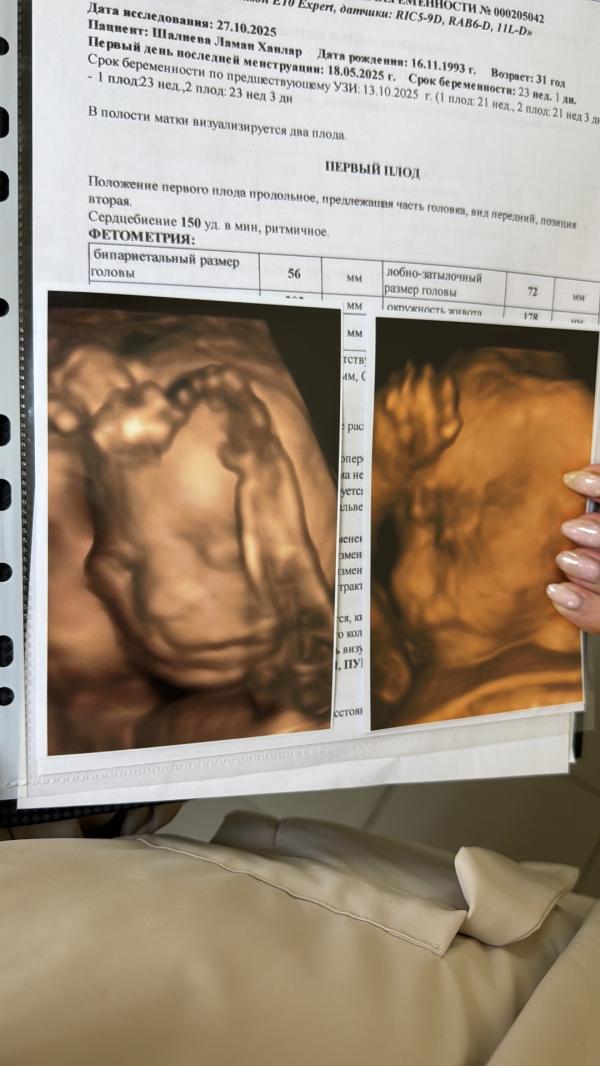

, в Узи студии детально все осмотрели деток и нет никаких многоводий😏Зря волновалась (детки здоровые 23 недели мальчик 650 грамм девочка 550🤩теперь интересно стало на 23 неделе у кого какой вес был?

Если смотреть на фото от экрана мальчик слева, а девочка справа?)